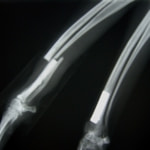

橈尺骨骨折 : 症例1 | 症例2 | 症例3 | 症例4 | 症例5 | 症例6 | 症例7

: 症例8 | 症例9 | 症例10 | 症例11 | 症例12 | 症例13 | 症例14

: 症例15 | 症例16 | 症例17 | 症例18 | 症例19 | 症例20 | 症例21

トイプードル 右遠位橈尺骨短斜骨折のALPSによる内固定